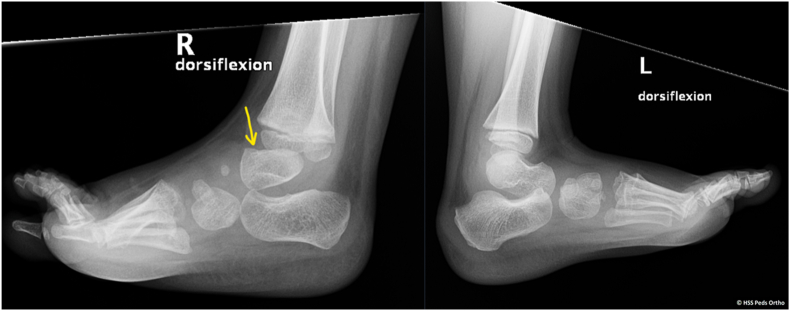

Key concepts: (1)Ponseti casting addresses all elements of clubfoot (midfoot cavus, forefoot and midfoot adduction, hindfoot varus, and equinus) in a systematic way that respects the natural kinematics of the foot.(2)Ponseti casting requires the use of gentle manipulation through the appropriate anatomical regions of the foot to ensure adequate correction, minimize residual deformity, and avoid iatrogenic deformity.(3)Efforts to minimize infantile distress will maximize the success of the Ponseti method. These include choosing appropriate cast and padding materials, providing a succinct casting plan, and optimizing brace tolerance.(4)Common undesirable consequences of casting include cast slippage, skin maceration, and iatrogenic deformities, such as tarsometatarsal abduction, hindfoot valgus, rocker bottom foot, and flat-top talus.